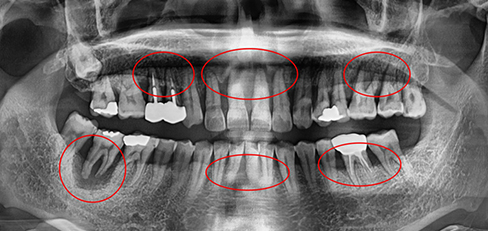

잇몸속 치아를 싸고 있는 치조골이 2/3 정도 소실되면

임플란트를 하고 그보다 치조골 손실이 적으면 비수술식

잇몸 치료를 통하여 자연치아를 최대한 살리려고 노력합니다.